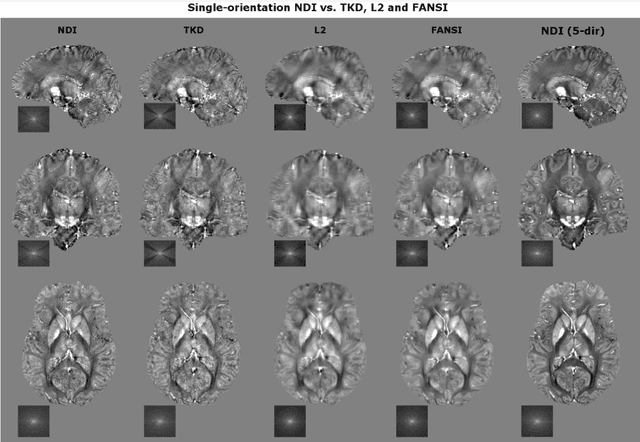

Abstract:We propose Nonlinear Dipole Inversion (NDI) for high-quality Quantitative Susceptibility Mapping (QSM) without regularization tuning, while matching the image quality of state-of-the-art reconstruction techniques. In addition to avoiding over-smoothing that these techniques often suffer from, we also obviate the need for parameter selection. NDI is flexible enough to allow for reconstruction from an arbitrary number of head orientations, and outperforms COSMOS even when using as few as 1-direction data. This is made possible by a nonlinear forward-model that uses the magnitude as an effective prior, for which we derived a simple gradient descent update rule. We synergistically combine this physics-model with a Variational Network (VN) to leverage the power of deep learning in the VaNDI algorithm. This technique adopts the simple gradient descent rule from NDI and learns the network parameters during training, hence requires no additional parameter tuning. Further, we evaluate NDI at 7T using highly accelerated Wave-CAIPI acquisitions at 0.5 mm isotropic resolution and demonstrate high-quality QSM from as few as 2-direction data.